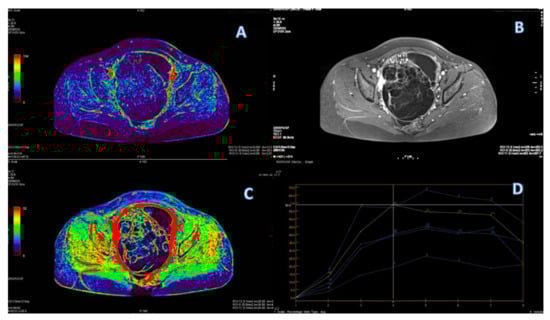

3.4. ROC Curve for LGSC vs. MOC

3.5. ROC Curve for HGSC vs. MOC